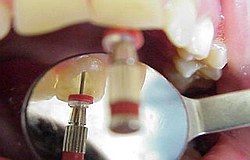

Die Nervnadel wird in den Nervkanal eingeführt

Wird nichts mehr empfunden so ist er tot und das tote Gewebe muss schnellstens aus dem Zahn entfernt werden (Wurzelkanalreinigung) bevor es im Zahn verfault und zu starken Schmerzen bis hin zur dicken Backe (Zyste) führt. Obwohl im Bild zur Verdeutlichung dargestellt ist eine Aufbereitung des Wurzelkanals (Nervnadel ragt über Wurzel hinaus ) über die Wurzel in den Kieferknochen bei der Zahnwurzelbehandlung natürlich nicht erwünscht. Um dies zu vermeiden müssen während der Wurzelbehandlung Röntgenaufnahmen angefertigt werden, die die ungefähre Länge der Wurzel berechnen lassen. Besser noch lässt sich die Länge der Wurzel elektronisch bestimmen .(Auf Wunsch Privatleistung). Ist die Wurzel an Ihrem Ende weit geöffnet kann es trotz aller Vorsicht zu einem ungewünschten Überaufbereiten und zu einer Überfüllung der Wurzel kommen. Dies beeinträchtigt dann oft den Erfolg. html Text zum Ausdrucken als pdf Datei. Falls über die Wurzelspitze hinaus in den umliegenden Knochen bereits Eiter aufgetreten ist und dieser den Knochen um den Zahn auflöst (das sieht man im Röntgenbild), so muss die infektiöse Wurzelspitze und die darum liegende Zyste entfernt werden .Im Prinzip ähnlich einem Pickel ausdrücken. Sobald der Druck (Eiter) dann heraus kann, geht sehr schnell der Schmerz bzw. auch die dicke Backe zurück. Der Vorgang nennt sich Wurzelresektion oder Apektomie. Die moderne Wurzelbehandlung umfasst Nickel-Titan-Feilen mit drehmomentregulierten Motoren gegen Instrumentenbruch, elektronische Längenmessung, Langzeit-provisorische Wurzelfüllungen mit provisorischen Langzeit-Füllungen. Alles leider Dinge die nicht in der Kassenleistung enthalten sind. So bleiben für den Patienten Kosten von ca. 60-480 EUR (je nach Schwierigkeit ) pro Kanal Aus manchen spezialisierten Prominentenpraxen wurde mir schon von Preisen bis zu 1200 EUR pro Kanal berichtet.

Wurzelbehandlung elektronische Längenmessung Vorgehen bei entzündetem Zahn Wurzelkanal